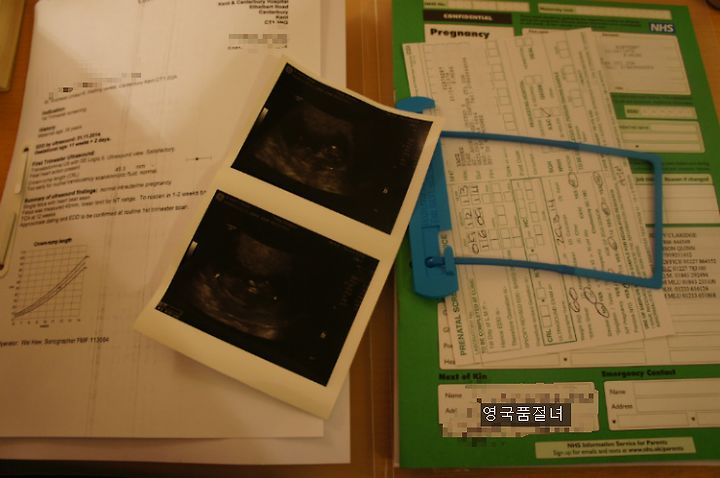

편지에는 초음파 검사를 받게 될 장소와 시간 등이 적혀 있었습니다. 그런데 그 외에 권유 사항으로 검사 한 시간 전까지 물을 약 1리터를 마시라고 했습니다. 그 정도의 물이 왜 필요한지는 잘 모르겠지만 저희야 시키는 대로 할 수 밖에 없었지요. 병원에 도착해서 서류를 제출하자 간호사는 마치 기다렸다는 듯이 저희를 초음파실로 안내했습니다. 병원에 올 때마다 항상 20-30분 정도 기다렸었는데 오늘은 다르더군요.

다시 스캐닝을 시작하자 간호사는 태아가 잘 보이는 위치에 스캐너를 고정시켰습니다. 그러자 귀엽게(?) 생긴 태아가 막 움직이기 시작합니다. 비록 5cm도 안 되는 작은 태아였지만, 제법 사람처럼 생겼더라고요. 꿈틀대는 것을 보니 놀라우면서도 신기했습니다. 이 녀석은 누굴 닮았는지 벌써부터 손발이 바쁘기만 합니다.

간호사는 스크린을 출력해 건네주면서 "아직 태아가 너무 작아 다운증후군 검사는 할 수 없으며 성별도 아직은 알 수 없다" 고 합니다. 약 2주 후에 다시 스캐닝과 피 검사를 받아야 한답니다. 2주 후 병원에 다시 와야 할 것 같기는 합니다만 임신과 관련된 모든 것을 직접 눈과 귀로 확인할 수 있어서 저희 부부는 그제서야 안도의 한숨을 쉴 수 있었습니다. 다만 필요 이상으로 마셨던 물은 스캐닝 이후에도 품절녀님을 조금 괴롭혔습니다. 병원에 나서면서도 화장실만 세 번을 더 들락날락했으니까요. ㅎㅎ